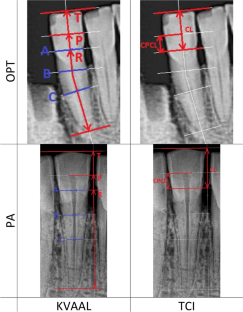

The analyzed material originates from the medieval necropolis of the Vinča—Belo brdo site. During the research, 60 periapical (PA) and 30 orthopantomographic (OPT) images were analyzed. On each analyzed tooth, age assessment was performed using both TCI and Kvaal techniques. The obtained values of dental estimated age were compared with age estimated by anthropological analysis, and the deviations between the estimated and chronological age were analyzed in relation to the assessment technique, type of dental radiograph, tooth group, sex, and age.